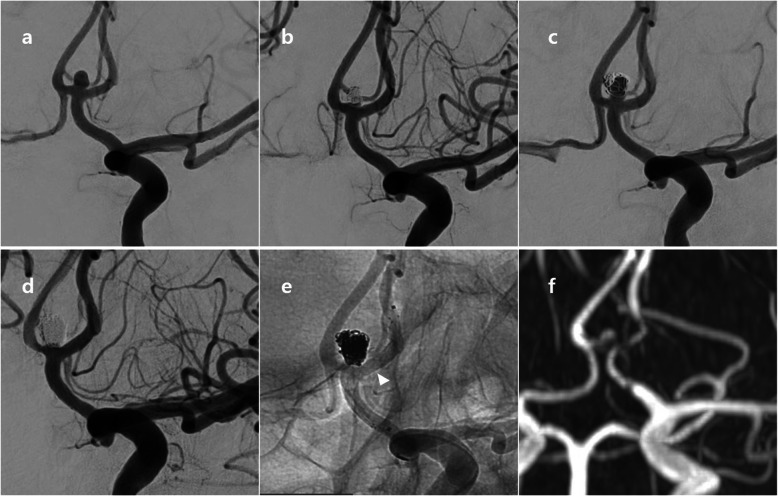

A 57-year-old male patient came into the emergency room with severe bursting headache. Ruptured Acom aneurysm was noted. Maximal size of aneurysm was 4.5 mm and neck size was 3.1 mm. Emergent EVT was performed and immediate post-embolization angiogram showed neck remnant occlusion (class II). After 1 year, cerebral angiography revealed a recurrence of aneurysm. Ipsilateral A1–2 stent-assisted coil embolization was done with neck remnant occlusion of sac (class II). After 1 year after retreatment, MRA revealed a more recurrence of aneurysm neck. These findings are described in Fig. 2.

A 57-year-old patient with recurrent Acom aneurysm. Initial angiogram showed a ruptured Acom aneurysm; maximal height 4.5 mm, neck size 3.1 mm (a). Immediate post-embolization image (b) showed neck remnant occlusion without sac filling (class II). After one year, cerebral angiography (c) revealed a recurrence of aneurysm. Stent-assisted coiling (arrowhead) was successfully performed, but neck remnant was still observed (d and e). After one year after retreatment, MRA revealed a more recurrence of aneurysm neck. Acom = anterior communicating artery; MRA = magnetic resonance angiography